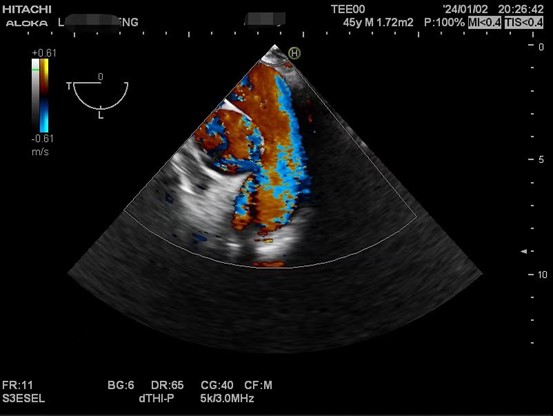

肝硬化患者术前合并症较多,术中血流动力学波动剧烈,围术期可能发生严重低血压、心内血栓形成、肺栓塞、左室流出道梗阻、心室收缩舒张功能不全等危急事件,给麻醉管理带来巨大挑战。TEE是将超声探头放在食管中段或胃底,从心脏后方持续观察心脏结构和功能,避免肺气对成像的影响,图像清晰且不影响手术的操作,是肝移植术中重要的监测手段之一。美国心脏超声协会及美国心血管麻醉医师学会均推荐肝移植术中常规使用TEE。目前美国各大移植中心术中麻醉科术中常规使用TEE进行持续监测。

以下是肝移植术中TEE监测的图像。